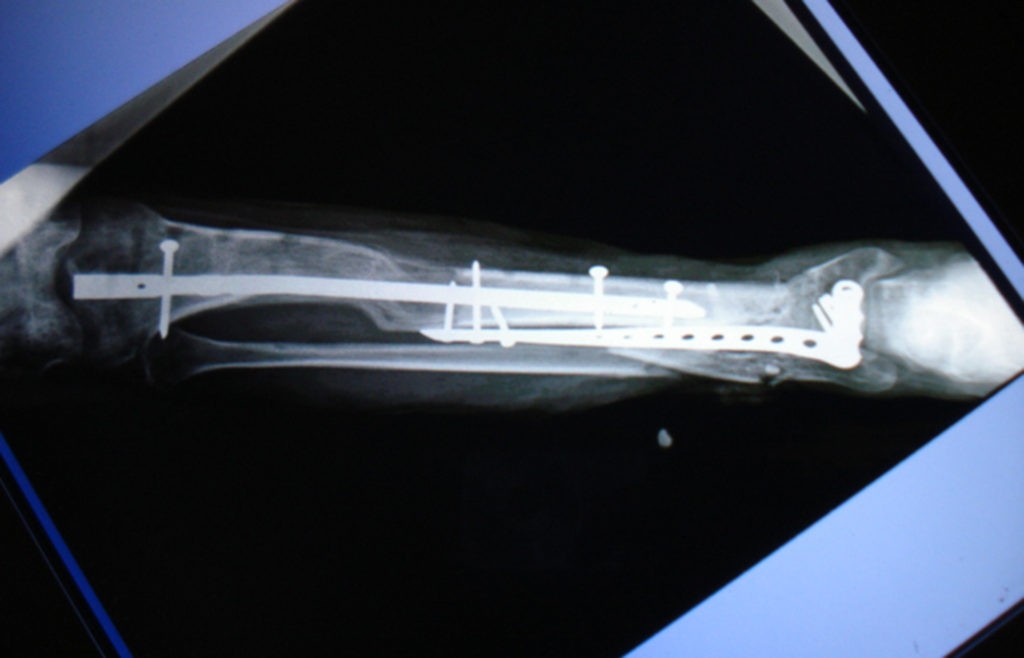

La doctora Fryda Medina Rodríguez, Directora General de la UMAE y quien encabeza el equipo de cirugía, explicó que esta técnica consiste en varios procedimientos: primero se retira el tejido muscular muerto, después se coloca una barra y un tornillo -que permanecen fijos a la extremidad-, y se realiza una incisión en la parte superior del hueso.

Posteriormente se coloca una esponja que ayuda a la regeneración de los tejidos. El aditamento empuja la masa muscular sin obstruir los vasos sanguíneos, y se cubre con piel el tejido expuesto.

Explicó que la elongación ósea permite que el hueso se alargue un milímetro por día, al hacer girar el tornillo 45 grados cada seis horas, día y noche; acción que el paciente debe realizar una vez que es dado de alta del hospital.

De esta manera se logra que la masa ósea, músculo, piel y tejidos se regeneren hasta alcanzar los centímetros de longitud perdidos en menos de un año.